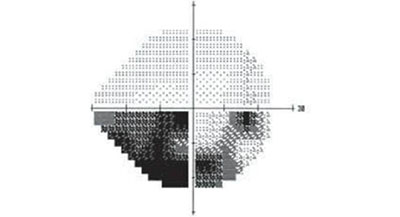

視野指的則是眼睛看向正前方時所能看到的空間范圍。在檢查中,視野常被劃分為四個象限,下圖就是一位青光眼患者的視野檢查結(jié)果,圖中黑色部分為視野缺損的部分。